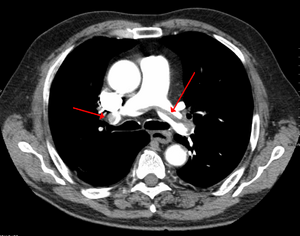

SaddlePE.PNG

Chest spiral CT scan with radiocontrast agent showing multiple filling defects both at the bifurcation ("saddle" pulmonary embolism) and in the pulmonary arteries.

التصوير الطبقي المحوسب

التصوير الطبقي المحوسب للرئة والمصحوب باستخدام الصبغة المشعة في الوريد أصبح واسع الانتشار والاستخدام في تشخيص المرضى المشتبه بإصابتهم بالانصمام الرئوي، لهذا النوع من التصوير حساسية تبلغ 83% ودقة نوعية تصل إلى 96%.[24].[25]